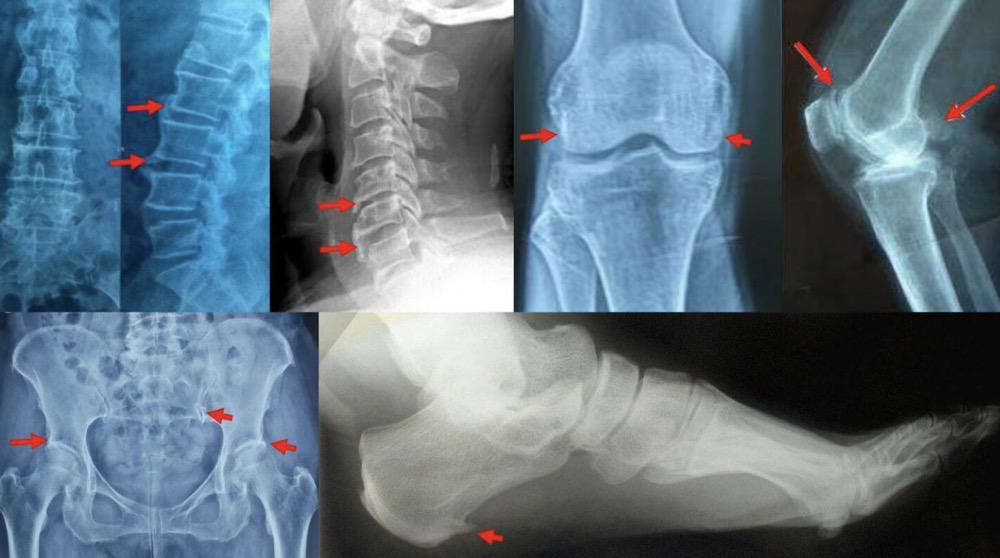

骨刺

骨刺是什麼?能治好吗? ezgoe

每日小课堂👉骨质增生 骨刺

什么是骨刺?明明不是什么大病却为何疼痛难忍?

骨刺不是你眼中厌恶的"刺头",骨刺除了让你疼痛,它还会帮你!